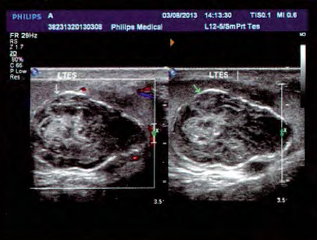

外科专科检查:左侧睾丸可触及一4cm×3cm肿物,质韧,轻压痛,附睾未触及异常。透光试验阴性。右侧睾丸、附睾及双侧精索未扪及异常,腹股沟区未扪及肿大淋巴结。肝、肾功能未见异常。血人绒毛膜促性腺激素(B—hCG)及甲胎蛋白(AFP)检查均在正常范围。B超检查显示左睾丸大小约5.0cm×3.0cm×2.8cm,内部回声不均匀,内可探及大小约3.2cm×2.4cm×2.1cm不均质包块回声,内呈低回声与稍高回声相间存在,周边呈高回声,包块周边可见短条状血流信号,其内可见星点状血流信号,考虑左睾丸表皮样囊肿。

初步诊断:左睾丸肿瘤(表皮样囊肿)。经过充分术前准备,择期行左睾丸肿瘤剜除术。行术中冰冻切片,结果示睾丸表皮样囊肿。 术后病理诊断:左睾丸表皮样囊肿伴异物巨细胞、胆固醇结晶及钙化。

睾丸表皮样囊肿临床少见,是一种睾丸的良性肿瘤,恶变率较低,仅占睾丸肿瘤的1%。本病常见于20—40岁的男性,以右侧睾丸发病为主,常以阴囊内肿块为首发症状。彩色多普勒是诊断睾丸肿瘤的主要手段之一。在诊断睾丸表皮样囊肿,其准确率高达90%。典型表现为肿物周边界限清楚,有强回声壁,肿物内大部分为低回声,部分中心为强回声,呈所谓的“靶环样”图像,内部无或仅有少量血流信号。目前睾丸表皮样囊肿的诊断依据病理学结果,不推荐睾丸穿刺活检,如为睾丸结核或恶性肿瘤,穿刺后会增加播散及转移的风险。睾丸表皮样囊肿是少见的睾丸良性肿瘤,超声对本病的诊断有较大意义,术后病理结果明确诊断。及早进行保留患侧睾丸的肿瘤剜除术,随访效果满意。